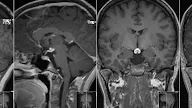

Post a Comment for "Schizencephaly Closed-Lip"